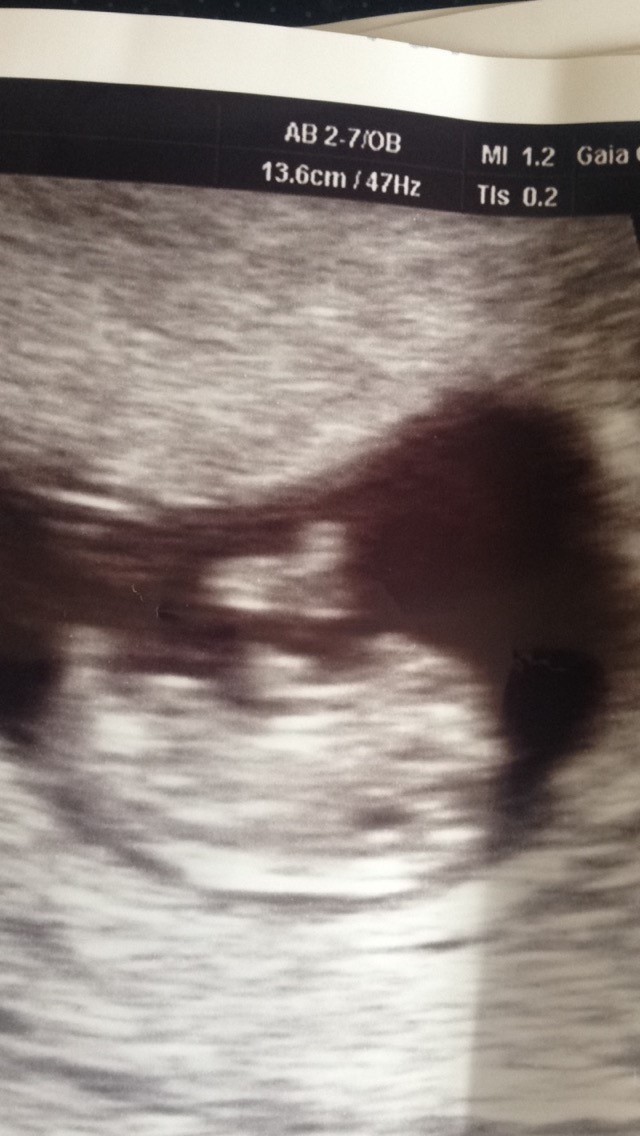

Så har vi været til trygheds scanning i uge 9+4 og alt var bare fint ❤️ Så nu vil jeg da ønske alle andre tillykke med graviditeten også.

Vedhæftede fotos (klik for at se i fuld størrelse)